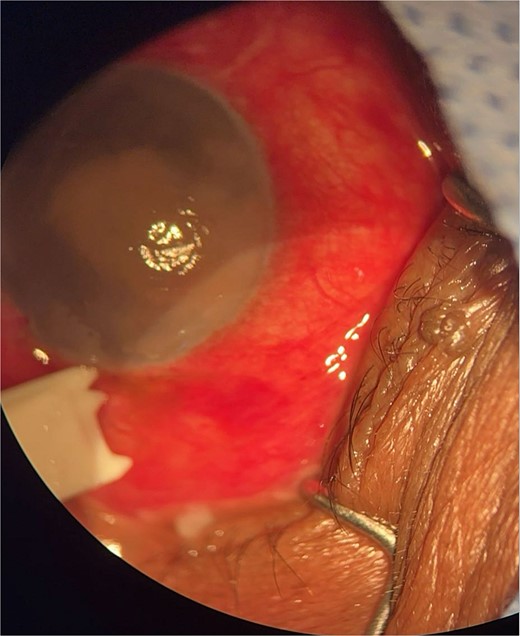

Patient 4: A 74-year-old Sudanese male visited the emergency room with severe left eye pain and loss of vision. His visual acuity was PL; examination showed hypopyon (Fig. 7). B-scan demonstrated vitritis (Fig. 8). He underwent emergency vitreous tap and intravitreal antibiotic therapy.

Surgical microscope examination showing hypopyon, chemosis, ciliary, and conjunctival injection in patient 4.